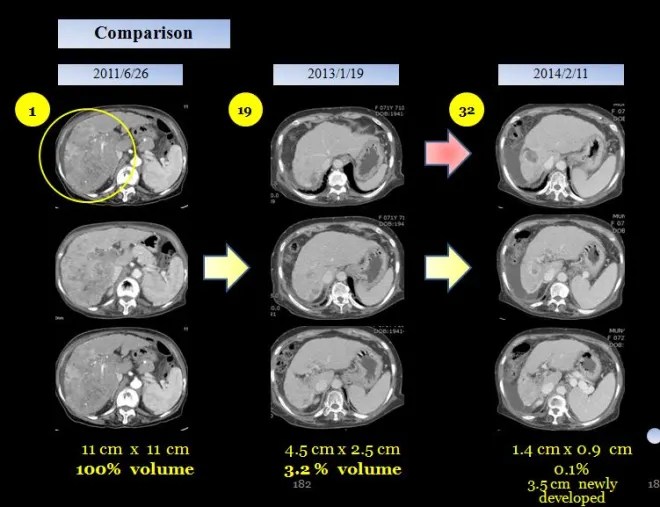

18 개월만에 간의 종양이 거의 체적대비하여서 4% 정도로 줄어들었고 2014 년도 3월에 통합의학대회에서 본인이 강의하기 전에 환자에게 CT 를 찍어볼 것을 권유하였다.

이분은 광주분이라 거의 내원을 하지 않고 전화상담과 약물만 꾸준히 지어서 복용하였는데 만 3년이 넘은 2014년 봄에는 더욱더 종양이 줄어들었지만 부분적으로 재발소견을 보였다.

3) 2014년 2월 11일

이 환자는 2014년 2월에 암이 거의 없어진상태에서 이전종양은 초기에 비해 0.1 % 정도로 감소하였으나. 새로이 다른부위에 3.5cm 종양이 보였는데, 이후에 치료를 받지 않았다.